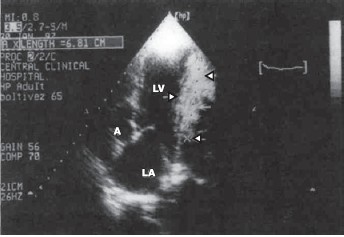

С другим примером целомической кисты сердца встретились у пациентки В., 54 лет с жалобами на боли в области сердца. Данные двухмерной трансторакальной и чреспищеводной интраоперационной ЭхоКГ были одинаковыми: выявлялось округлое образование с гипоэхогенным содержимым, окруженное плотной капсулой, размером 9х6,2 см, несколько деформирующее полость ЛЖ в области заднебоковой его стенки, что не отражалось на глобальной систолической функции ЛЖ (рис. 1).

Рисунок 1. Двухмерная ЭхоКГ сечения 4 камер сердца и аорты пациентки В., 54 лет.

В ближнем поле изображения — по заднепатеральной стенке ЛЖ — целомическая киста перикарда (пунктиром обозначены размеры кисты).

Здесь и на рис. 2—5: ЭхоКГ — эхокардиограмма; ЛЖ — левый желудочек.